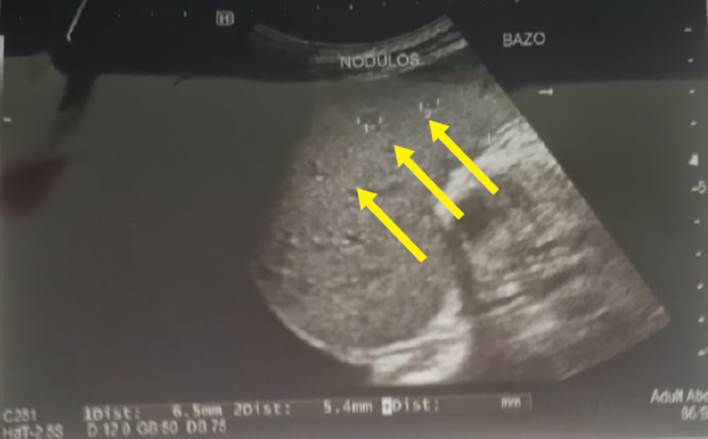

En la Tabla 1 se muestran los exámenes de laboratorio que se realizaron durante la hospitalización del paciente: baciloscopia en esputo con resultado negativo, baciloscopia en orina con resultado 5 BAAR y baciloscopia en heces que resultó positiva (+), ecografía torácica con reporte de líquido libre en ambos hemitórax, un volumen de 400 ml en el hemitórax izquierdo y 150 ml en el derecho; radiografía de tórax que muestra derrame pleural bilateral con predominio izquierdo (Figura 1); ecografía abdominal con hallazgos de esplenomegalia y nódulos hipoecogénicos (Figura 2); test de adenosina deaminasa en líquido pleural con valor 33. Los resultados de carga viral para VIH fueron 181 000 copias/ml y CD4: 63.

El tratamiento actual de los pacientes con TB asociada al VIH incluye la aplicación de un tratamiento antituberculoso eficaz, el uso de la TARV concurrente, la prevención de comorbilidades relacionadas con el VIH, el tratamiento de la citotoxicidad de los medicamentos y la prevención de situaciones adversas como el SIRS 16. Como control de la adhesión del paciente y respuesta adecuada al tratamiento antituberculoso, se realizaron baciloscopias, cultivos con enfoque en los sistemas donde se involucró la TB, así como exámenes de diagnóstico por imagen que comprueben la resolución de lo presentado antes del tratamiento. Con respecto al TARV, se evaluó la clínica para hacer un seguimiento de la evolución del paciente. Además, se realizó la valoración inmunológica y virológica mediante el recuento de CD4+ y ARN viral, respectivamente. Asimismo, en la Figura 2 se hallaron nódulos hipoecogénicos, que en un principio se sospecho que era un linfoma, aunque también podría ser propio de la infección existente. Para tener un diagnóstico certero será necesario realizar otro estudio por imágenes luego de varios meses de tratamiento y verificar si es que existe resolución o no.